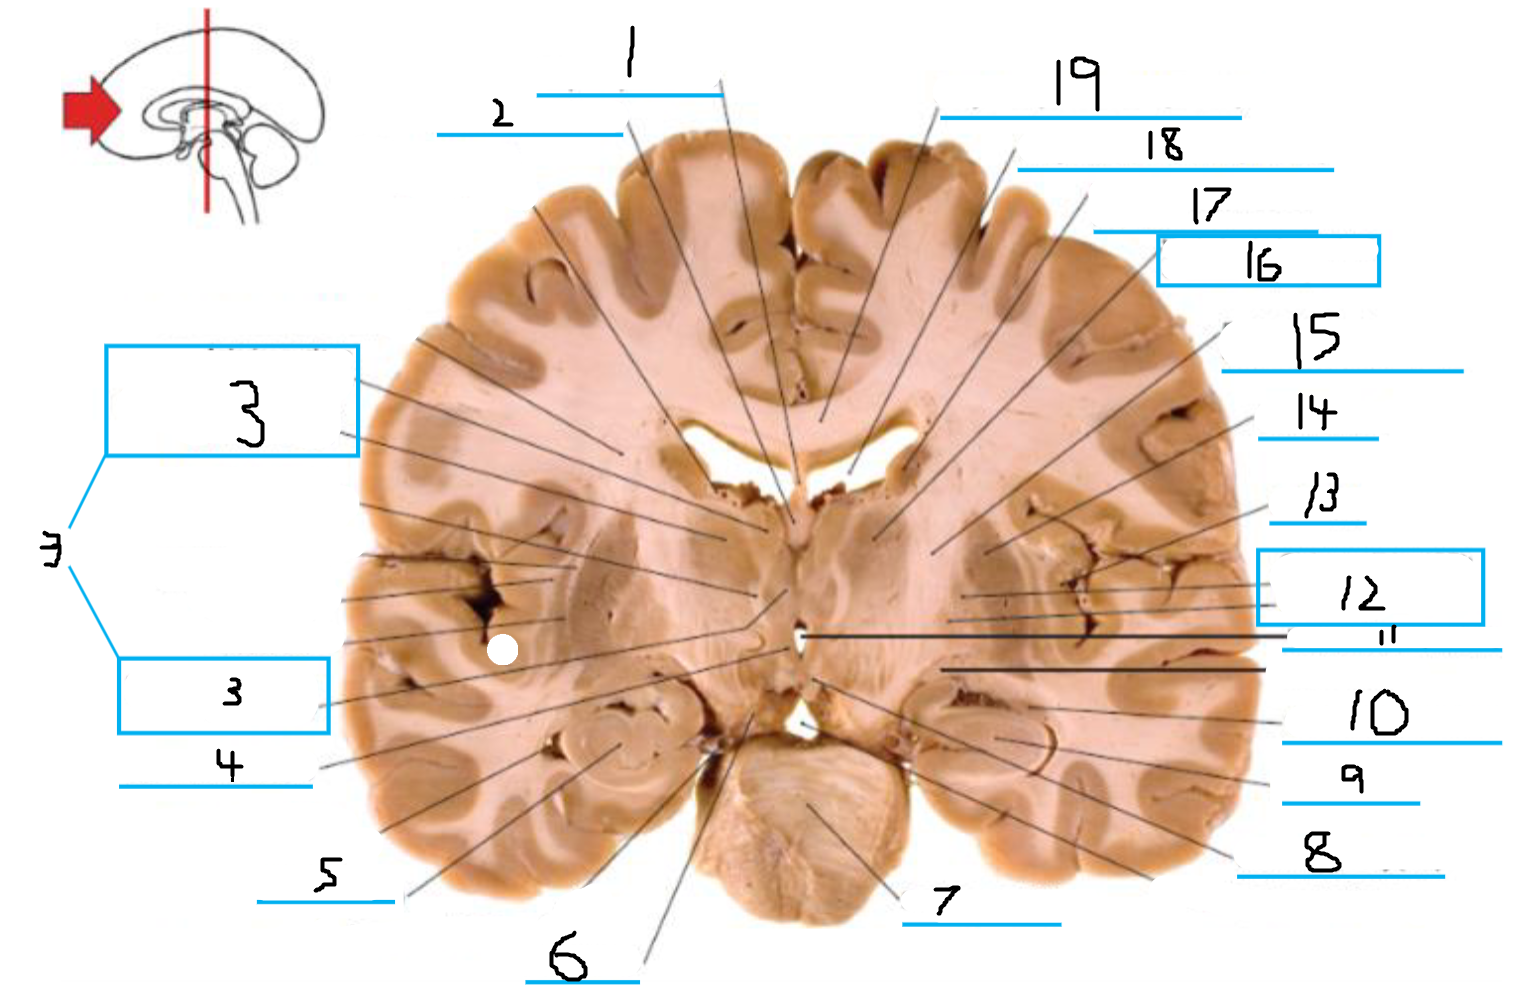

#1 is the:

Corpus Callosum

#2 is the:

Septum Pellucidum

#3 is the:

Lateral Ventricle

#4 and #9 is the:

Globus Pallidus

#5 is the:

Insula

#6 and #8 is the:

Anterior Commissure

#7 is the:

Optic Chiasm

#10 is the:

Putamen

#11 is the:

Internal Capsule

#12 is the:

Caudate